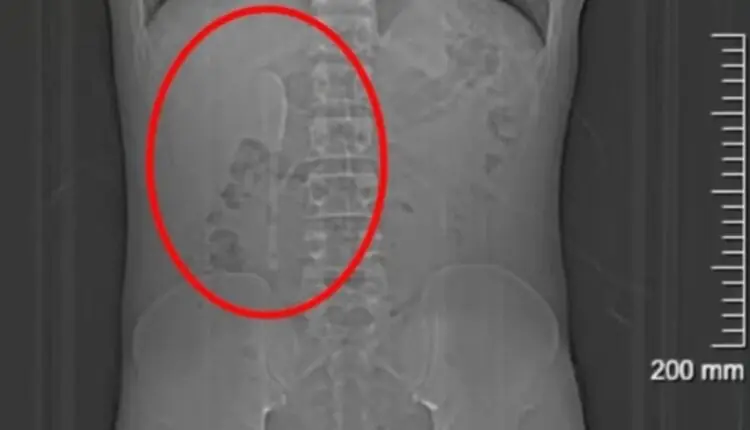

No hospital, exames de imagem revelaram o insólito diagnóstico: uma colher de aproximadamente 15 centímetros estava alojada em seu duodeno, parte inicial do intestino delgado. Segundo os médicos, a remoção era complexa devido à superfície escorregadia do objeto e à sua posição, que oferecia risco de perfuração intestinal, inflamações ou sangramentos.